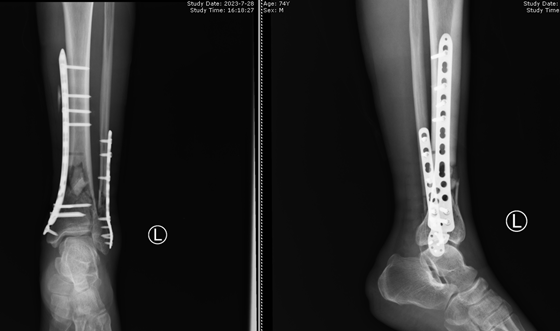

针对谭爷爷的特殊情况,骨科创伤组在林开胜副主任医生的指导下,进行详细的病情讨论并制定了详细的手术计划:予以外侧常规切口固定腓骨骨折,内侧予以微创钢板接骨技术(Mipo技术)固定胫骨骨折,这样既可以最大限度的保证骨折端及皮肤的血运,又可以缩短手术时间及减小创面,大大提高了患者术后恢复质量,同时得益于国家的集采政策,内固定等耗材价格大幅下降,也打消了患者看病贵的顾虑。

当杨雷主治医师将手术方案告知患者及家属后,患者及家属均表示同意,谭爷爷欣喜的表示:“湘雅常德医院可以根据我的实际情况为我量身定制治疗方案,真是让人放心!”。完善一系列术前准备后,谭爷爷的手术顺利完成,术后换药时谭爷爷看着自己的伤口不由得感叹了一声:“好!小切口解决了我的大问题!”

“微创钢板接骨技术”(Mipo技术)是随着BO理念发展而诞生的技术,其核心就是避免骨折端直接暴露的同时提供合理的复位和一定强度的固定,保护骨折端血运,为骨折的更好愈合提供良好血运基础,同时减少了患者手术部位暴露时间,降低了手术费用,减轻了患者身体负担,缩短了术后住院时间,为患者术后快速康复提供了有力的保障,目前该技术已可运用于全身多处长骨骨折。当然Mipo技术也不是万能的,不恰当的运用该技术会导致骨折移位、畸形愈合甚至不愈合,徒增患者痛苦。湘雅常德医院骨科始终致力于为患者打造更好的治疗方案,“因病施治,因人施治,规范施治”。此次谭爷爷“小切口解决大问题”也是我科卓越医疗、卓越服务的很好体现。